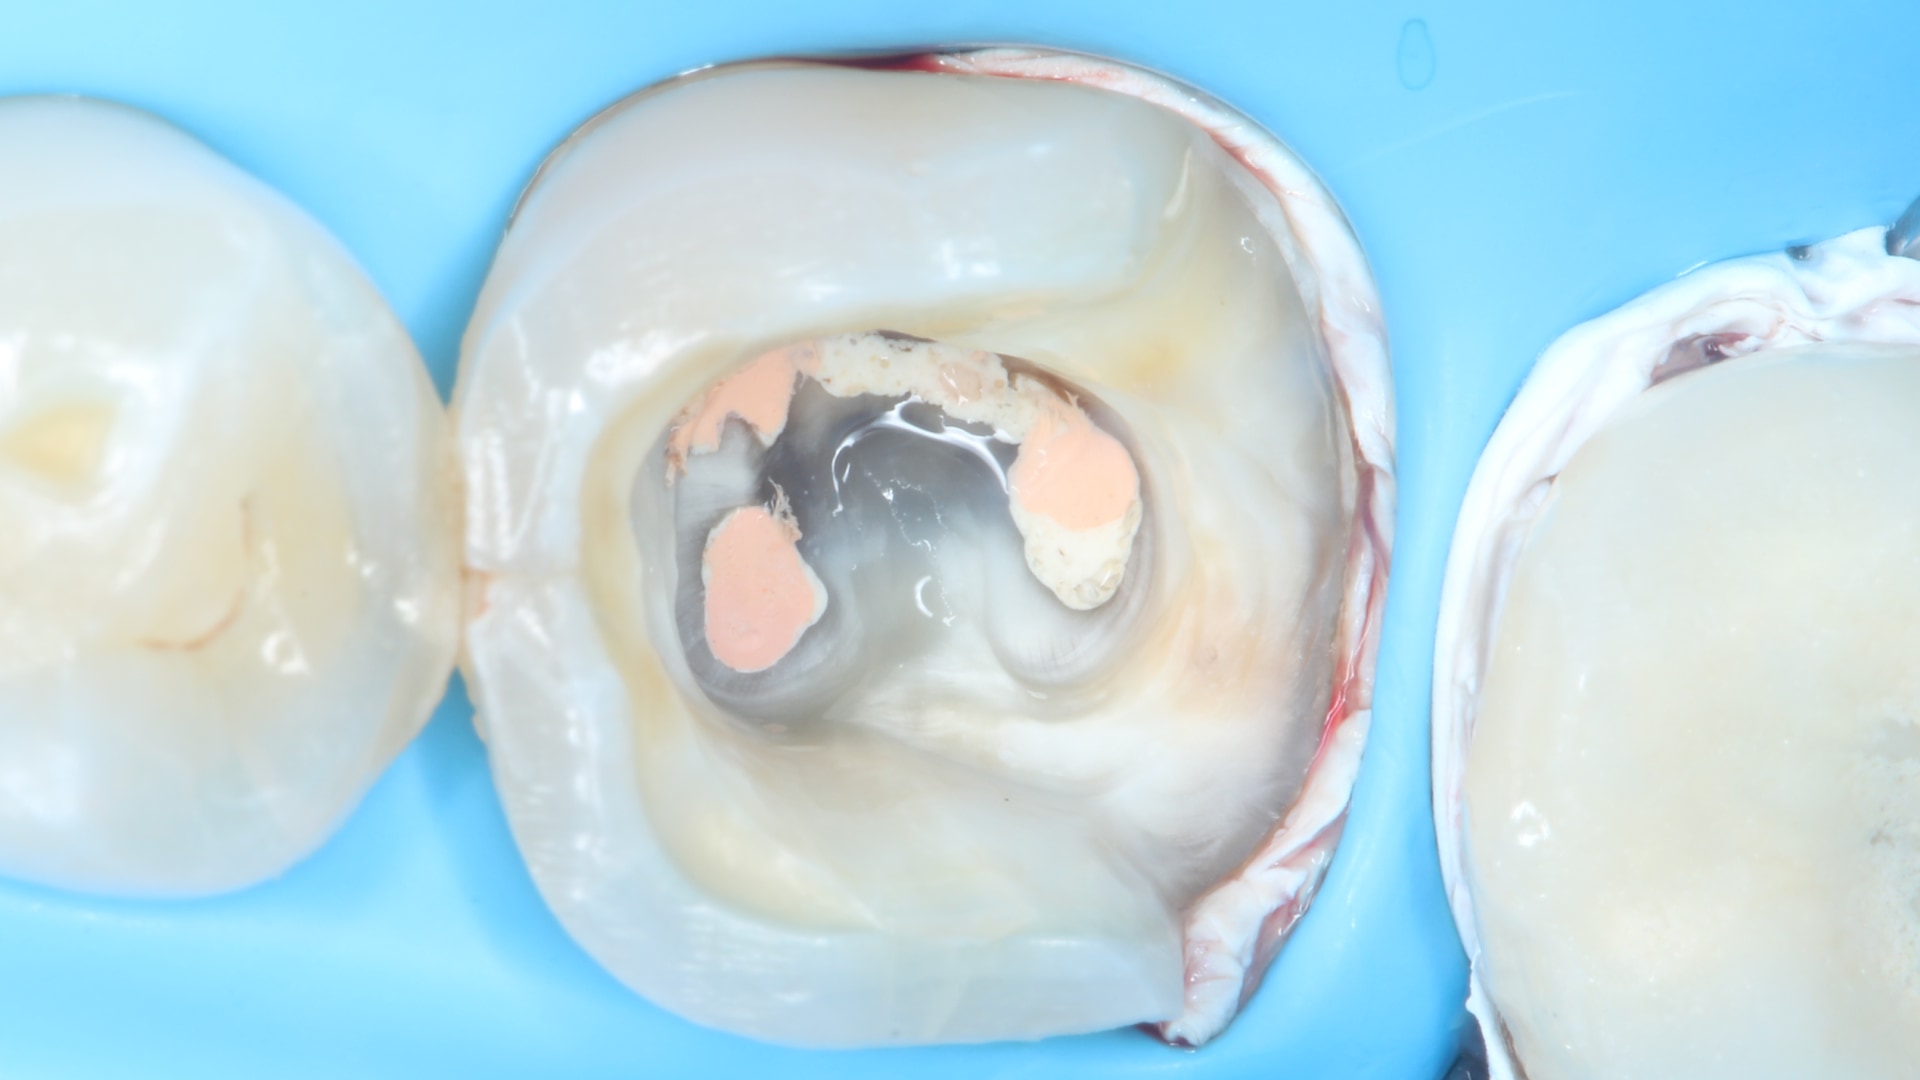

Intra-Operative: The old composite was completely removed establishing a proper enamel margin for good peripheral seal. Rubber Dam isolation was applied and the distal margin of the tooth needed deep margin elevation. DME was performed along with sealing the pulp chamber. The tooth was then prepared for an endocrown indirect restoration.